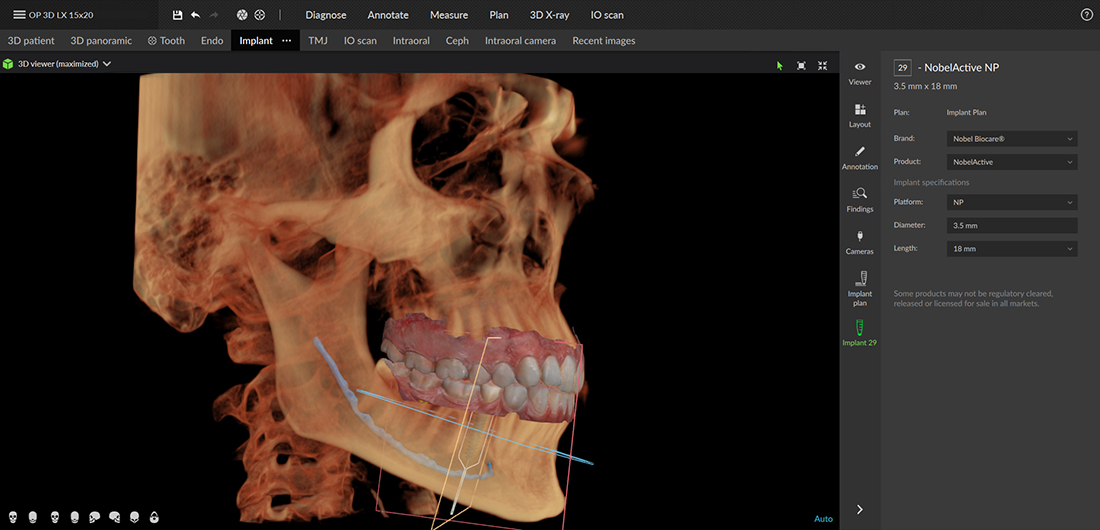

Implantátum behelyezés

Legyen szó szóló implantátum behelyezéséről vagy All-on-4 technológia alkalmazásáról, a DEXIS OP 3D LX lehetővé teszi a többdimenziós képalkotást a műtét előtti diagnózis felállításához valamint a lehető legprecízebb implantátumbeültetés támogatásához.

A 3D technológiára épülő multimodalitású képalkotó platform lehetőségei a fogászati felvételi igények teljes spektrumát lefedik, az endodontiától a legösszetettebb implantációs esetekig.

Ez az új generációs rendszer rugalmas látómezőt (FOV) kínál, a készülékkel többféle felvétel is készíthető: 5 x 5 cm-es részleges, 3-4 fogról készülő felvételtől egészen a 15 x 20 cm-es teljes arckoponya CBCT–ig, ami jelenleg a legnagyobb látómező a DEXIS OP 3D-n.